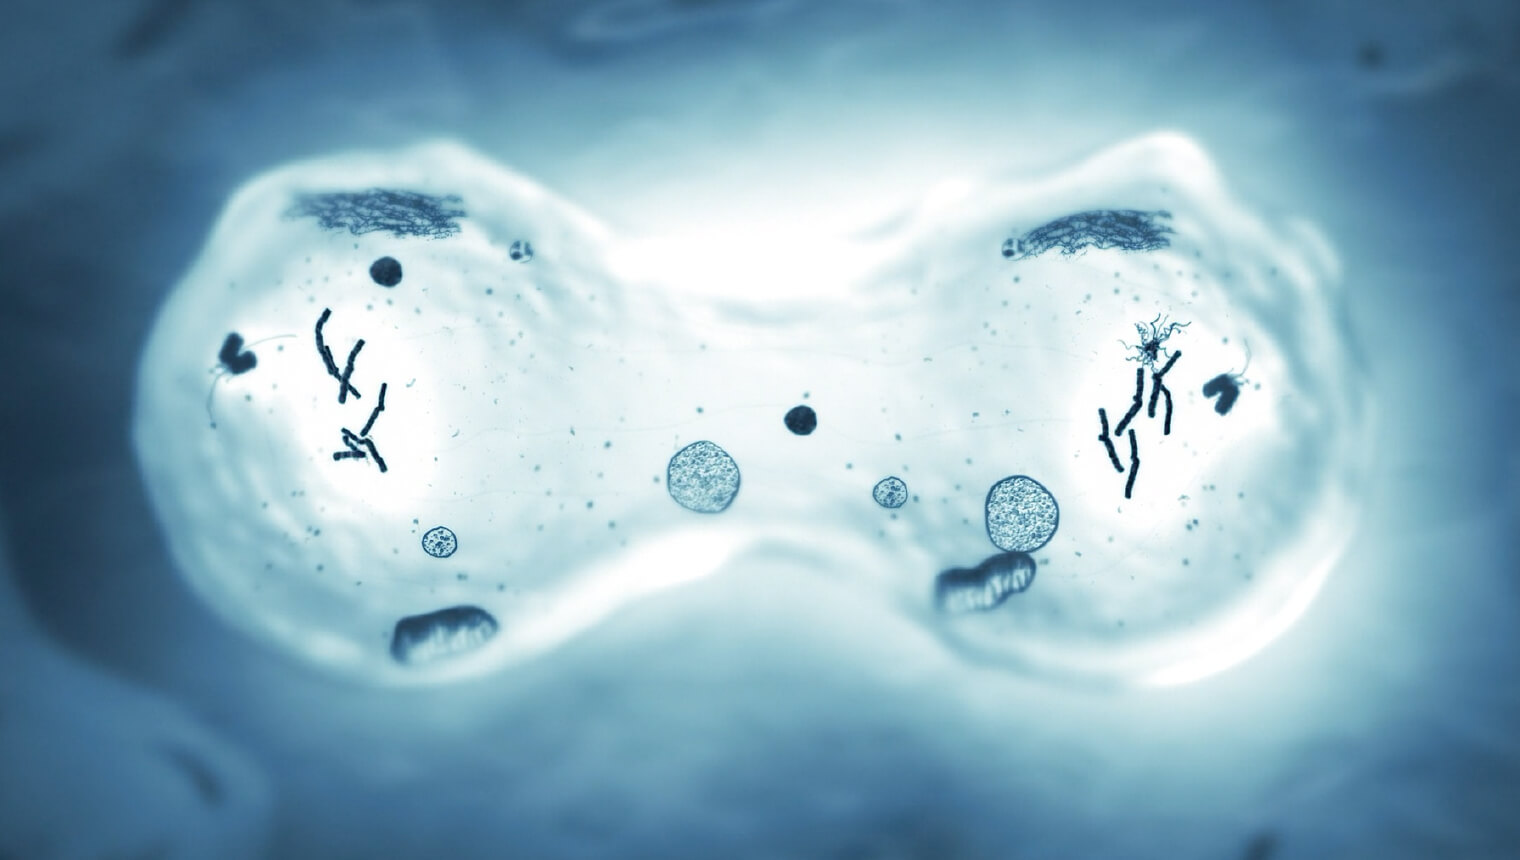

診療内容:ゲノム医療・免疫療法・再生医療・老化細胞除去・疾病予防